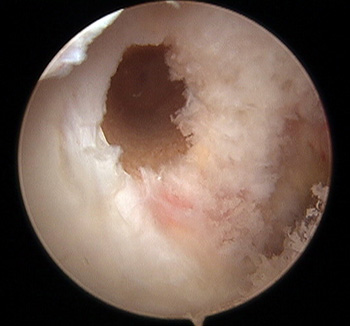

maestu1_fig7

Figura 7: vista artroscópica desde portal anterolateral de fijación femoral en simple banda en una rodilla izquierda.